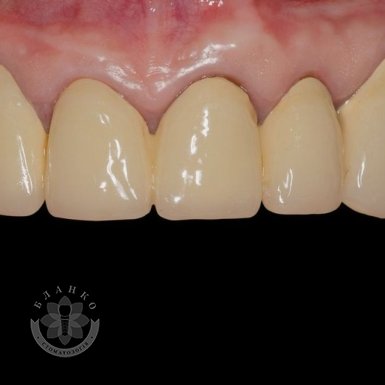

Зубна імплантація — це сучасне та надійне рішення для відновлення втрачених зубів. У стоматологічній клініці Бланко ми пропонуємо імплантацію зубів «під ключ», що означає повний комплекс послуг — від діагностики до встановлення коронки, без прихованих платежів та несподіваних витрат.